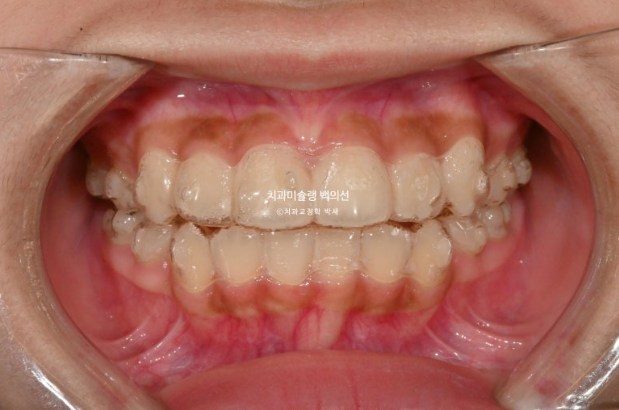

25.09

중심선은 잘 맞으며 앞니 교합은 적절합니다.

어금니 교합은 1급이고 좋습니다.

25.10~25.09

그 사이 두번째 큰어금니까지 모두 나와 잘 배열되었습니다.

총 치료기간은 1년 11개월, 중간에 쉰기간을 빼면 실제로 1년 9개월정도 됩니다.